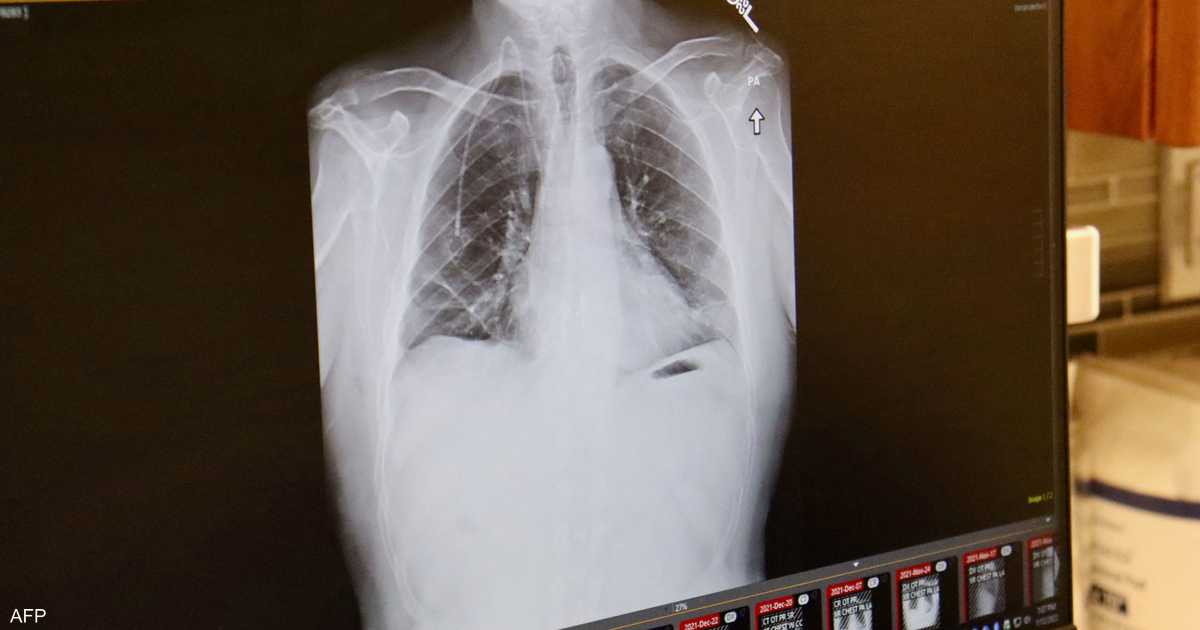

ويضيف أن سرطان الرئة، وخصوصا السرطان الغدي ( نوع من السرطان يبدأ في الغدد التي تفرز مواد مثل المخاط أو السوائل في أنسجة الجسم وقد يصيب الرئة)، لا تظهر أعراضه في المراحل الأولى، مثل السعال وألم الصدر وضيق التنفس، إلا عندما يكون الورم قد انتشر، ولهذا تشخص أغلب حالات هذا المرض في مرحلة متقدمة.

وشهدت السنوات الأخيرة تحسنا كبيرا في تشخيص هذا المرض، حيث ارتفع متوسط البقاء على قيد الحياة لدى المرضى الخاضعين للعلاج إلى أكثر من عشر سنوات، بعدما كان لا يتجاوز سابقا سنة واحدة.